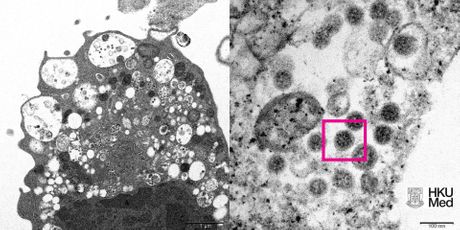

Univerzitet u Hong Kongu objavio je fotografiju omikron soja virusa korona, dobijenu uz pomoć elektronskog mikroskopa.

Naučnici Medicinskog fakulteta, uključujući stručnjake iz oblasti patologije i virusologije, uspeli su da naprave mikrofotografiju ćelije (Vero E6) bubrega majmuna zaražene sojem omikron, navodi se u saopštenju naučnika prosleđenom Sputnjiku.

Kako su precizirali, na fotografiji sa malim uveličavanjem vidi se oštećenje ćelija sa otečenim vezikulama koje sadrže male crne virusne čestice.

Na mikrofotografiji sa većim uveličavanjem, vide se agregati virusnih čestica sa spajkovima (šiljcima) virusa korona na površini.